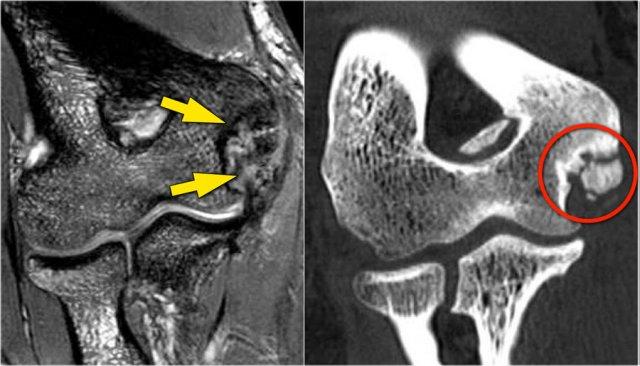

Pseudodefect of the capitellum

Đây là một phát hiện mà bạn thường thấy trên các hình ảnh mặt phẳng coronal.

Trông có vẻ giống như một tổn thương sụn xương, nhưng nếu bạn nhìn vào hình ảnh mặt phẳng sagittal, bạn sẽ nhận thấy rằng hình ảnh mặt phẳng coronal đi qua phần không có khớp phía sau của chỏm con.

Vì vậy, khi khuỷu tay duỗi hoàn toàn, một phần của chỏm quay thực sự nằm phía sau bề mặt sụn khớp của chỏm con.

Trên hình ảnh mặt phẳng coronal, chúng ta sẽ quan sát thấy chỏm quay được bao phủ bởi sụn và đối diện với nó là phần không được bao phủ bởi sụn của chỏm con, phần này thường có phần không đều.

Pseudo-loose body

Một phát hiện phổ biến khác là một mảnh mỡ nhỏ mà bạn sẽ thấy trên hình ảnh mặt phẳng đứng dọc, trông giống như một dị vật nhỏ tự do hoặc một khuyết sụn.

Điều này có thể được giải thích nếu chúng ta nhìn vào bề mặt khớp của mỏm khuỷu.

Thông thường mỏm khuỷu có hai mảnh sụn với một vùng nhỏ ở giữa, được lấp đầy bởi mỡ.